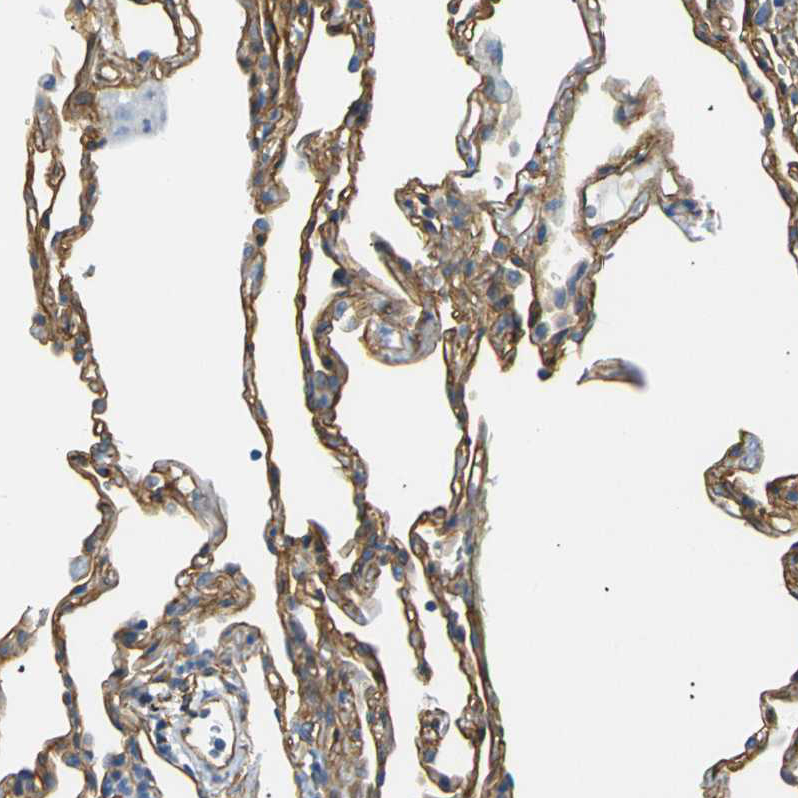

Immunohistochemistry analysis in human lung and skeletal muscle tissues using HPA012685 antibody. Corresponding SPTBN1 RNA-seq data are presented for the same tissues.